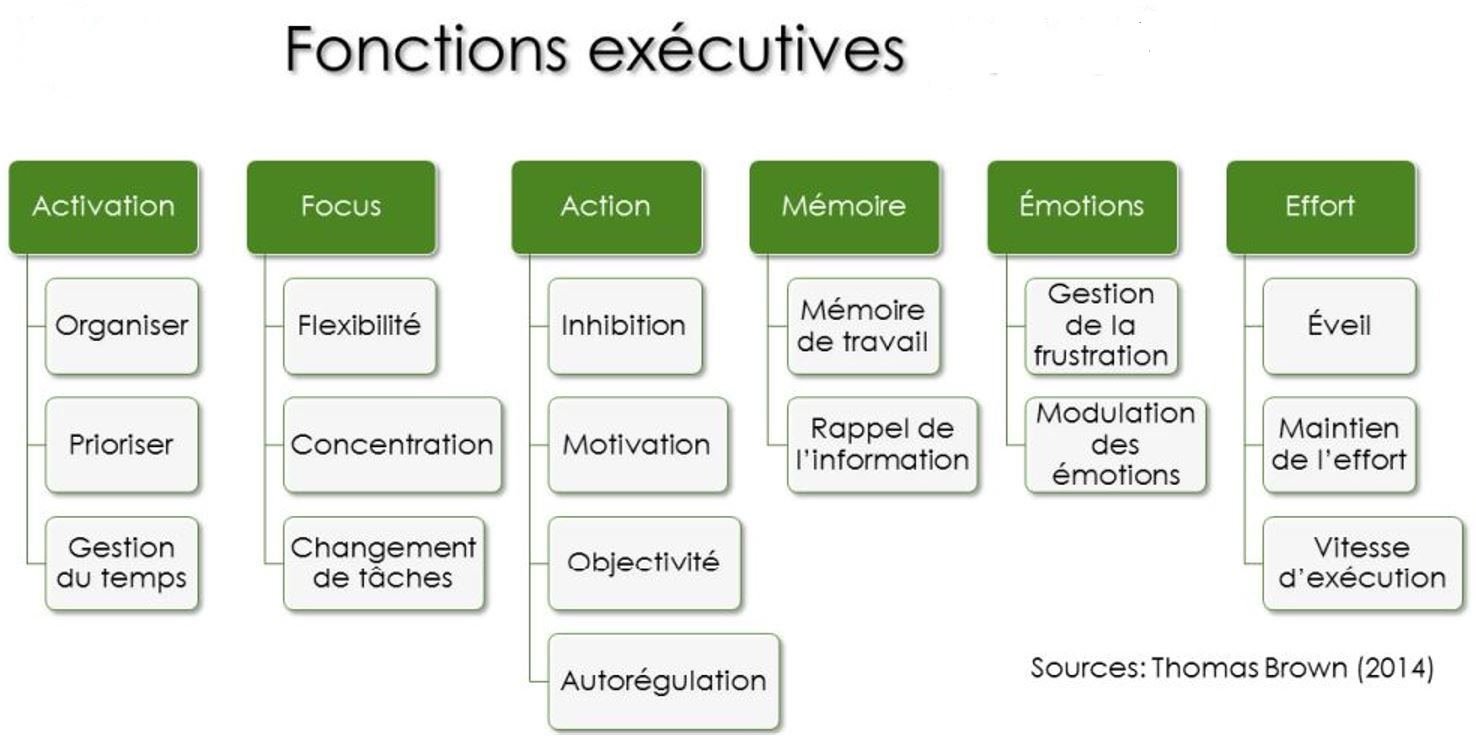

► C’est un déterminisme génétique (donc héréditaire), qui entraine, du point de vue neurologique, une mauvaise régulation de deux neurotransmetteurs principalement (excès ou carence) , la Dopamine et la Noradrénaline, notamment au niveau du lobe frontal et spécialement sa partie derrière le front, le cortex préfrontal (schéma ci-contre). – La Dopamine sert à réguler les circuits de la récompense, du plaisir, de l’énergie, de l’attention, de la vigilance et de la motivation. – Leur présence irrégulière dans les connexions entre les neurones au niveau de l’axone (schéma ci-dessus) entraine une inconsistance de l’attention, du plaisir et de la motivation, notamment pour les tâches ou les relations de la vie de tous les jours. ► Le cortex frontal sert à programmer, planifier, inhiber des comportements impulsifs, mais aussi avoir une bonne flexibilité mentale. Il doit en effet être capable de s’interrompre si quelque chose de prioritaire survient en pleine action. — Pour être attentif, on a besoin d’une bonne transmission de la dopamine dans ce cortex frontal, ce qui n’est pas souvent le cas avec le TDAH. – Cela se traduit de manière différente selon que l’on est dans une phase hyperactive ou hypoactive : – Si je suis hypoactif, c’est-à-dire avec peu d’énergie, je pense à une chose à faire qui me fait penser à autre chose, puis d’autres pensées arrivent encore. – Un haut potentiel associé à une des 8 formes formes d’intelligences recensées (mathématique, verbale, musicale, corporelle, visuelle, interpersonnelle, intrapersonnelle), peut construire une arborescence d’idées créative. – Mais souvent au final je n’ai rien fait, car je suis resté dans ma tête, et, de plus, je n’ai souvent rien mémorisé, car ce sont des pensées furtives non propices à la mémoire de travail. – Si je suis hyperactif, je commence une tâche, je l’interromps pour commencer autre chose puis autre chose sans lien avec la tâche prioritaire initialement commencée (hyperactifs). – j’ai fait une multitude de tâches ou j’ai parlé abondement, la plupart du temps sans intérêt par rapport à mes priorités et aux attentes des autres personne. ► Du point de vue neurologique, les fonctions exécutives sont regroupées en 6 familles (avec l’acronyme : A.F.F.A.M.É.E) : – ACTIVATION : s’organiser, structurer, synthétiser, prioriser, décider, initier la tâche en gérant le temps – FOCUS : maintien de l’effort et de la vitesse d’exécution, ou basculement vers une tâche prioritaire – ACTION : autorégulation des actions, ralentir, s’activer ou s’adapter selon les situations/personnes – MÉMOIRE : capacité à conserver et rappeler l’information en mémoire durant une tâche/conversation – ÉMOTIONS : savoir moduler l’émotion pour ne pas s’emporter facilement, savoir gérer la frustration – EFFORT : ne pas perdre l’intérêt dans la tâche et faire face aux difficultés dans un temps donné  ► Chacune de ces 6 familles de fonctions exécutives peut poser un problème si on a un TDAH. On parle aussi de syndrome dysexécutif. ⇒ Chacun peut faire son propre bilan neuropsychologique chez un neurologue moyennant finance, mais on peut résumer ci-dessous les principaux problèmes que rencontre la majorité des enfants et adultes TDAH : – Problèmes d’attention focalisée (concentration) et divisée (suivre plusieurs informations en simultané) – Problèmes de gestion des informations stockées dans la mémoire à court terme (mémoire de travail) – Capacité d’inhibition : il s’agit d’une difficulté à empêcher ou à freiner des comportements et paroles inadaptées. – Problèmes dans la formulation d’objectifs, l’anticipation, l’élaboration de stratégie et la prise de décision – Problèmes dans la planification, l’organisation, la gestion des priorités et la gestion du temps. ► Cette liste de déficits est insupportable pour ceux qui ont misé sur un style de vie ou un type de métier qui n’autorise pas ces dysfonctionnements. – Ces déficits des fonctions cognitives et exécutives peuvent être un obstacle si on veut construire une vie trop conventionnelle nécessitant de la rigueur et de la régularité, avec beaucoup de frustration et le sentiment de ne pas s’accomplir. – D’où la nécessité de bien se connaitre pour faire des choix de style de vie, d’objectifs et de métiers compatibles avec cette particularité neurologique, ainsi que respecter ses besoins et valeurs. – Toute forme de forte et saine motivation peut permettre de générer la dopamine et noradrénaline nécessaires pour avancer durablement sur ses projets. – Une bonne hygiène de vie, de l’exercice physique, des pratiques psychocorporelles pour calmer le mental permettront d’atténuer cette inconsistance en neurotransmetteur (voir plus loin le manuel d’auto-coaching). |